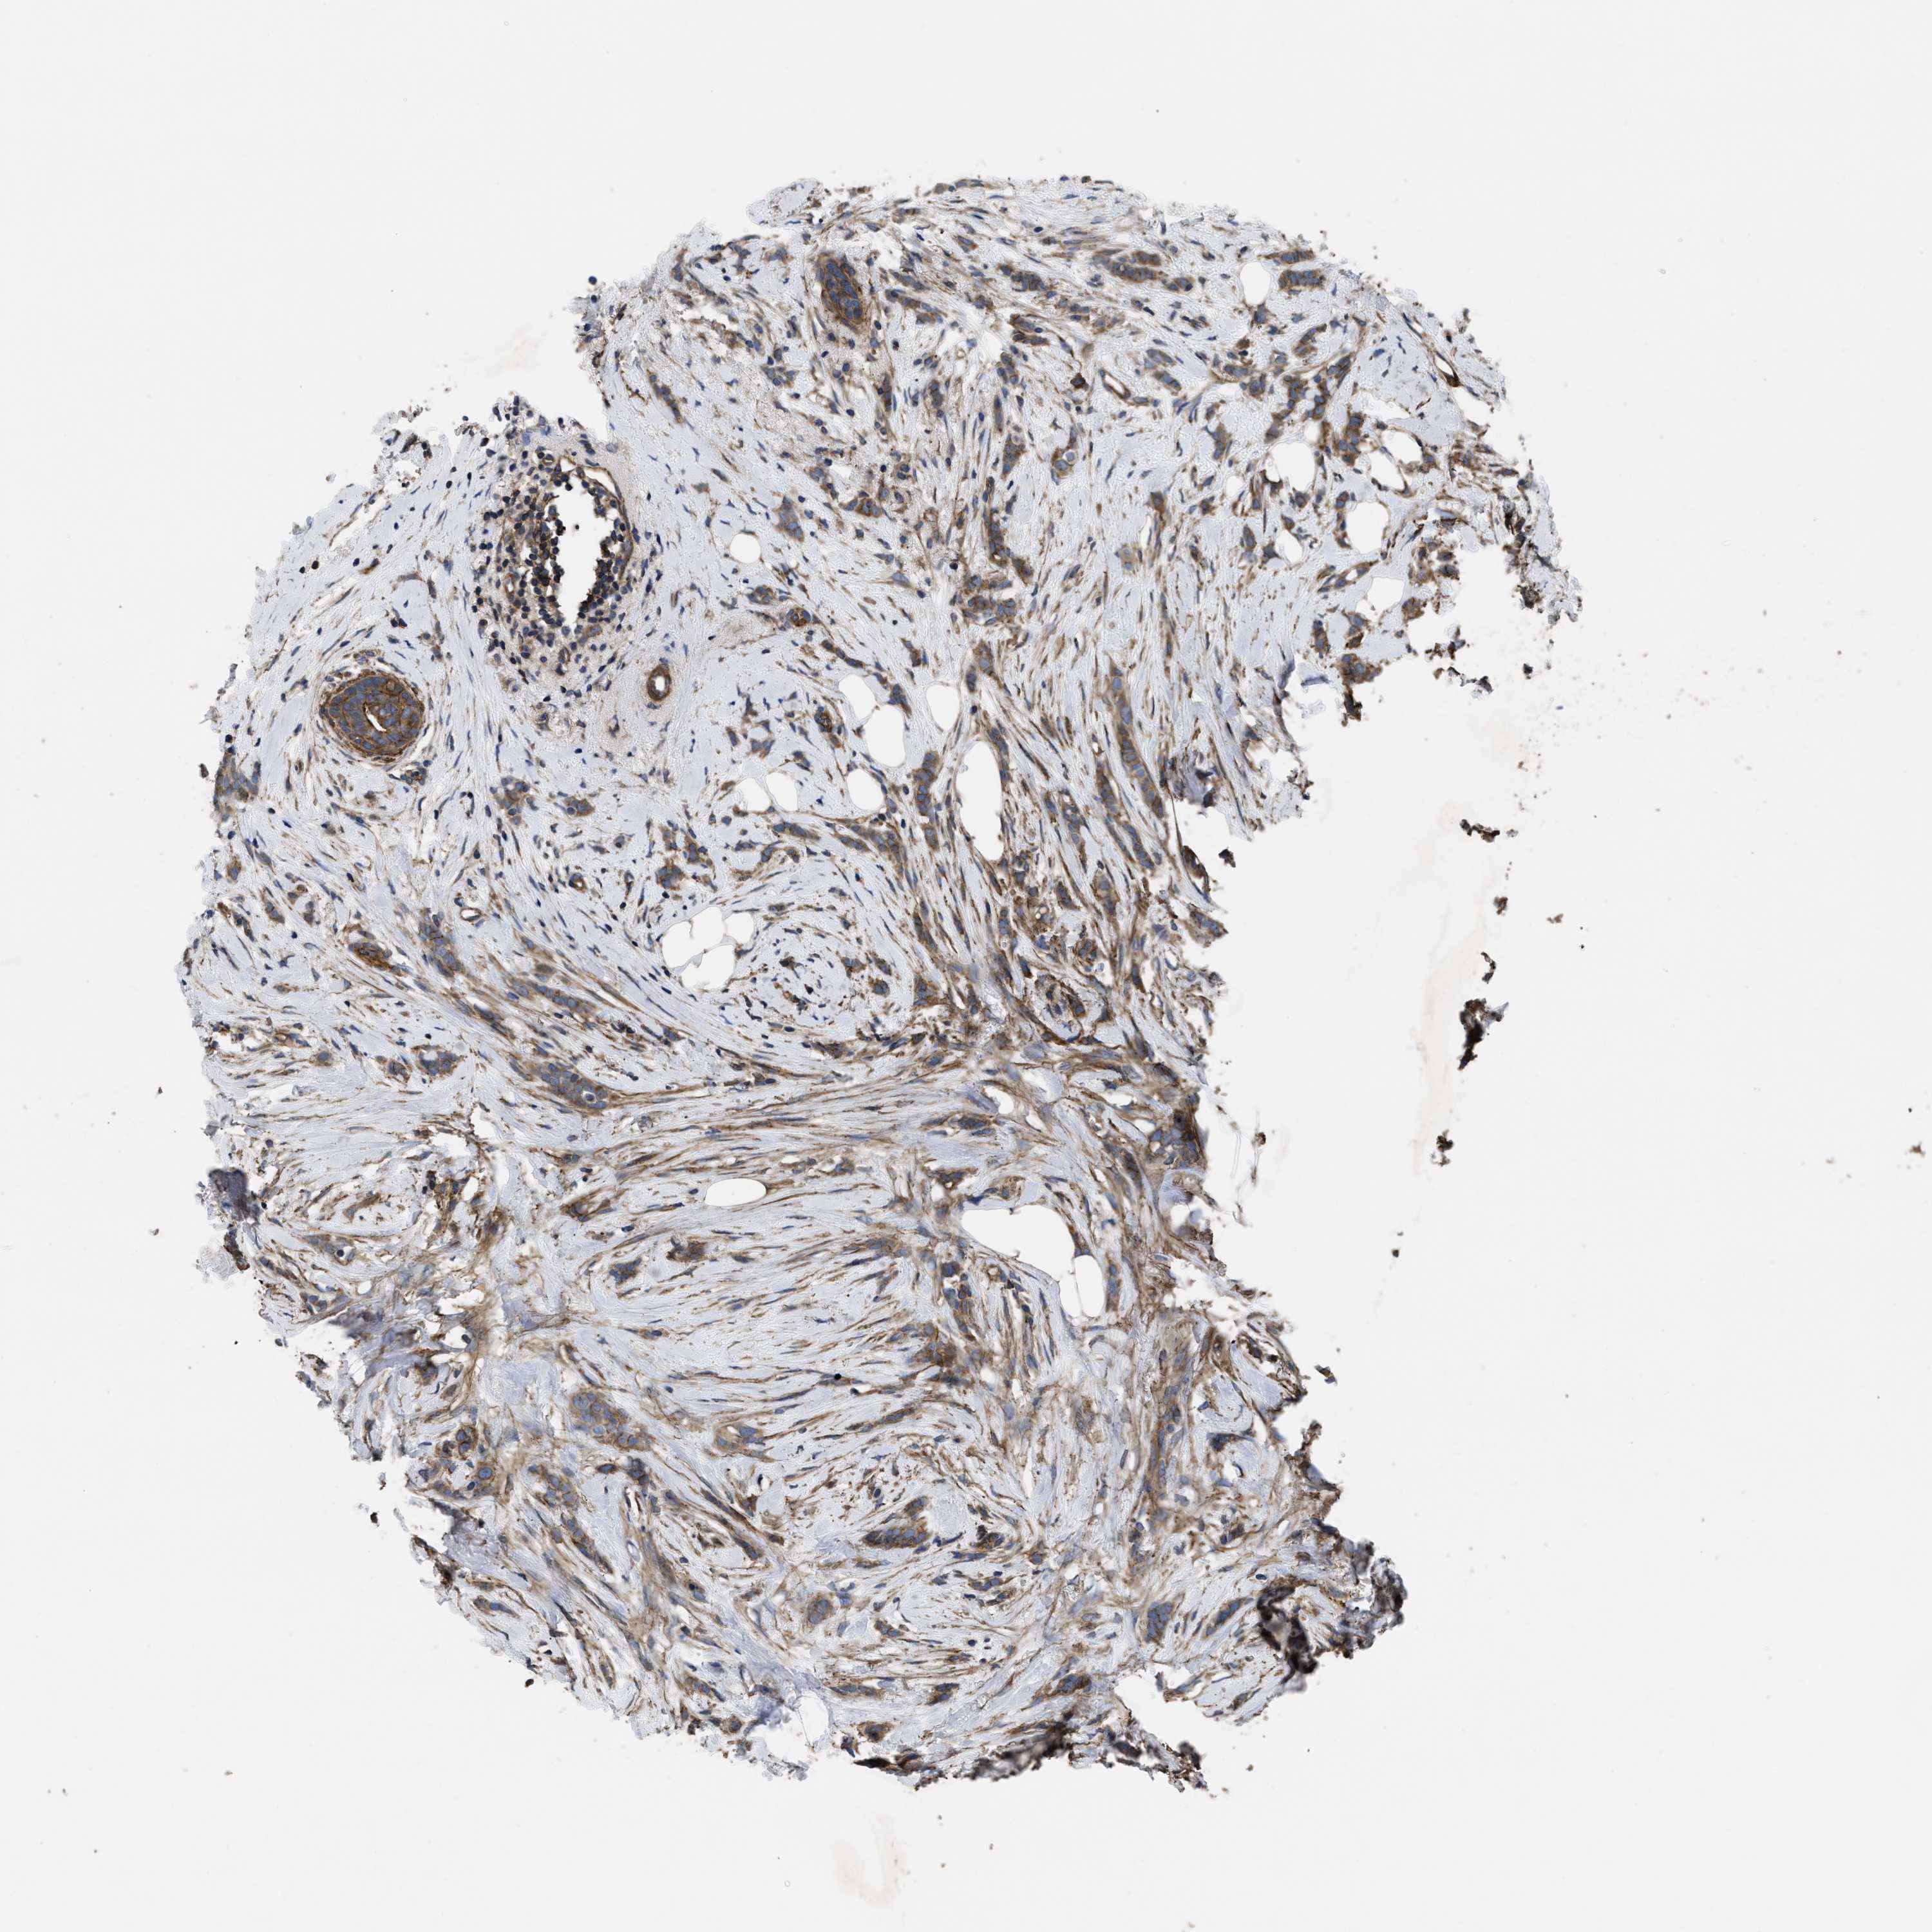

CANCER BREAST CANCER Show tissue menu

BRCA TCGA BRCA VALIDATION PROTEIN EXPRESSION